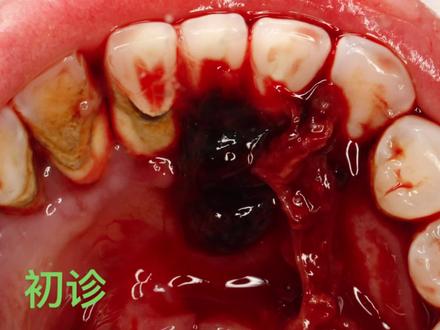

大家好,今天我们讲一个牙龈出血不止的案例啊,这名患者呢是一个四十岁的女性啊,中午就诊的,嗯,他说他今天上午呢,就一直牙龈就不断的老是出血, 出血停会止一会,停一会止一会,哎,到第四次出血的时候就怎么也止不住了,他就有点慌了,来到了他们周围的社区医院,那社区医院认为呢啊,这个病呢,他们治不了, 还是让他们来到我们这个三甲医院来看一看。到了我们医院急诊科以后呢,我一看这个患者啊啊,牙石非常多啊,给我一个出印象的很有可能就是慢性牙周炎引起的,那么啊,首先我们还是要排除他凝血是否有 障碍啊,全身有没有疾病啊,血液类的疾病,血压有没有升高之类的啊?血压没有升高啊,全身都是健康的,凝血功能也是正常的,那么 基本上确定是牙石刺激引起的,那牙齿刺激引起的一般都是啊,我们认为不仅是这个机械的刺激啊, 牙石机械的刺激,还有一些细菌引起的,这个牙龈长期的红肿啊,所以出血不止啊,这时候呢,有一急诊呢,不处理这种慢性的疾病啊,即使是出血啊不止,但是 啊,我们还是等到了下午两点半才进行处理的啊,在急诊是没有这个洁牙的设备的,所以请他到了两点半啊,那一周后的复查呢,可以看到牙 牙龈恢复的非常好,消肿了啊,一个是喊这个患者本身全身健康,所以他这个牙龈恢复的呢,也比较快。 嗯啊,这个从这个复查也可以看到,牙龈出血的主要原因还就是由于这个牙石引起的菌斑引起的牙龈的这个 红肿这个主要原因,所以说洁牙是非常重要的啊。好,今天的案例就分析到这里。